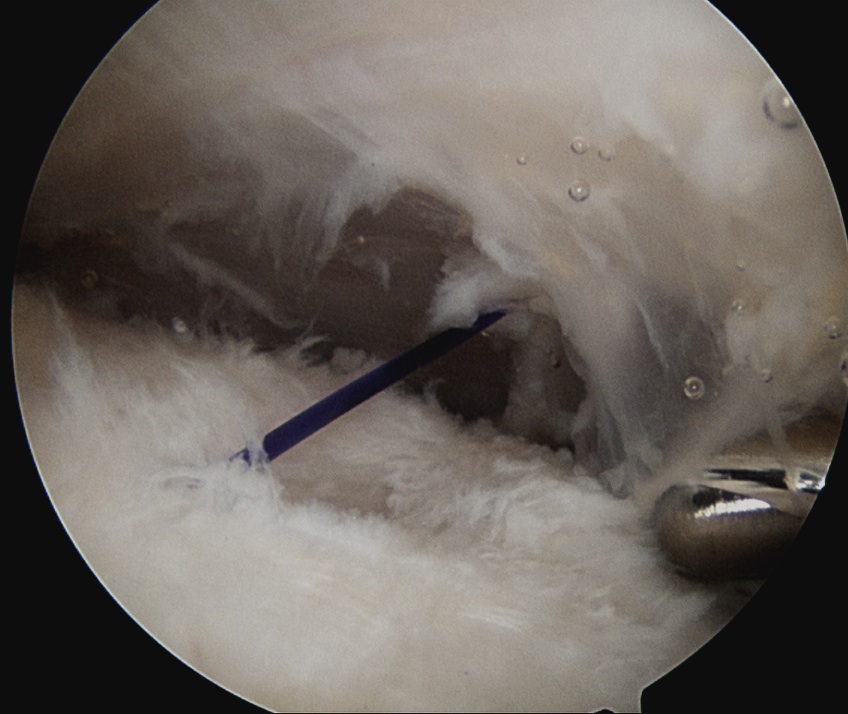

Camera in glenohumeral joint

- use spinal needle to identify center of PASTA

- pass 1 PDS to mark lesion

- camera into subacromial space

- use suture to identify area for tear completion

- cautery or knife to complete tear

- double row repair